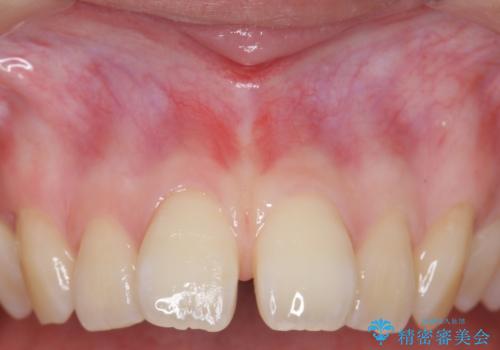

上唇小帯切除 矯正前の予防的外科処置

上唇小帯切除 矯正前の予防的処置